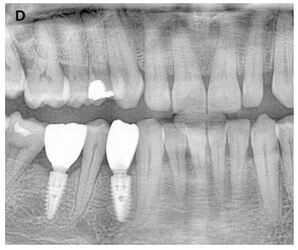

(A ) Right mandibular first and second molars with chronic periapical pathology due to unsuccessful endodontic treatments. (B ) Extraction of teeth, placement of immediate implants and filling of socket cavities with guided bone regeneration (1st postoperative week). (C ) Postoperative 5th month panoramic radiograph image. (D ) Follow-up radiograph at 12 months after completion of prosthetic restorations